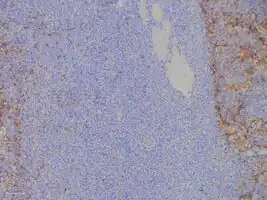

Micrograph of a plasmacytoma. -

Micrograph of a plasmacytoma. H&E stain.